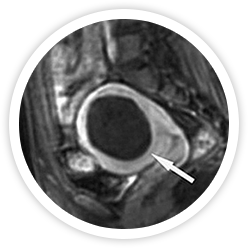

• 시술 2년 후 시술 2년 후

하이푸 시술 2년 후 절제된 근종은 MRI 조영증강영상에 확인 할 수 없을 만큼 완전히 흡수된